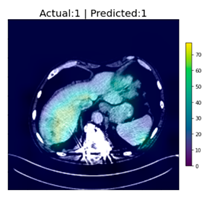

As an interesting sidenote: During the testing phase of the CNN classifier, an investigator noted that it appears that tumors in certain body regions appeared to have a higher rate of classification accuracy than images of other regions. Although it was not in the original plan, an impromptu experiment was conducted to test this hypothesis. From the 1700 original samples, those that contain tumors in specific regions of the body, i.e., the liver and lungs, were grouped together. The reason we chose these two regions is that patients residing in the Asia-Pacific region are more susceptible to cancers in these regions [20], and symptoms of cancers in these regions also tend to be ignored by patients in their early stages because these symptoms can be insignificant. If these types of cancer can be detected at an early stage, then treatments with higher rates of success can be prescribed.

The two groups, liver cancer, and lung cancer were trained and tested separately. The final results appear to justify the earlier suspicions: the classification of tumors in the lung region achieved 98.126% accuracy, while the classification of those in the liver region achieved an astounding 100% accuracy. However, because their sample sizes are small, the results are not truly representative. It is, however, an interesting observation even though the results are not useful for the Grad-CAM experiment due to the small sample sizes. The following figures, Figure 7 and Figure 8, show the sample outputs of these experiments, where “Yes/No” indicates whether a tumor was detected, and the values of “1/0” are DeepLesion labels, where “1” indicates the image contains tumor”, and “0” indicates “has no tumor”.

Figure 8.

Examples of the classification of CT images containing liver tumors.